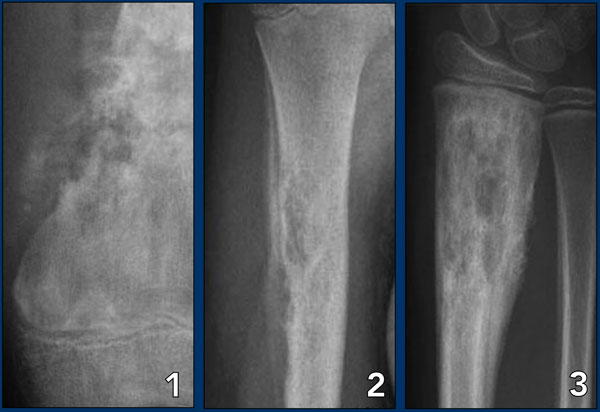

Aggressive periosteal reaction Aggressive periosteal reaction

Aggressive periosteal reaction (2)

1. Osteosarcoma with interrupted periosteal rection and Codman's triangle proximally (red arrow).

There is periosteal bone formation perpendicular to the cortical bone and extensive bony matrix formation by the tumor itself.

2. Ewing sarcoma with lamellated and focally interrupted periosteal reaction. (white arrows)

3. Infection with a multilayered periosteal reaction.

Notice that the periostitis is aggressive, but not as aggressive as in the other two cases.